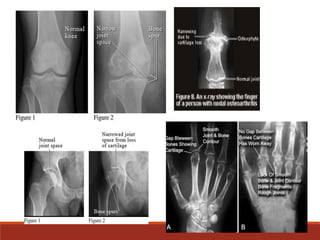

X-ray

It shows any damage

or other changes

related to

osteoarthritis to

conform the diagnosis

NORMAL ABNORMAL